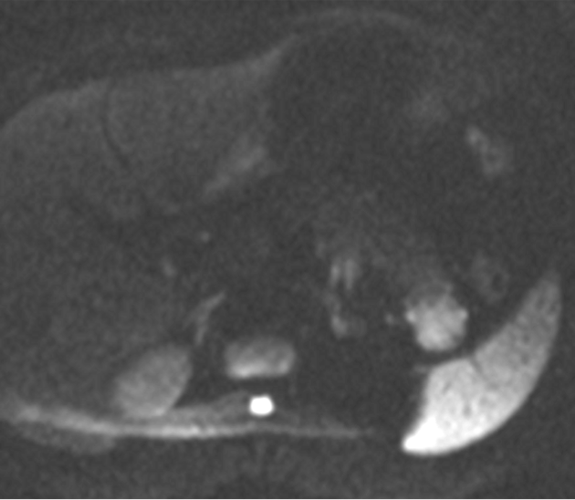

Hombre de 39 años con antecedente de fibrosis retroperitoneal.

Se solicita TC porque en RM externa realizada para control de la fibrosis retroperitoneal se informa de sospecha de neoplasia de cola de páncreas.

3. ¿Cuál es tu diagnóstico?

- A. Tumor pseudopapilar sólido pancreático con metástasis renales izquierdas.

- B. Linfoma pancreático -forma localizada- y lesiones atróficas renales izquierdas secundarias a fibrosis retroperitoneal.

- C. Lesión metastásica en páncreas de tumor primario renal.

- D. Pancreatitis autoinmune en contexto de enfermedad relacionada con la IgG4.

- E. Sarcoidosis con afectación pancreática y renal.